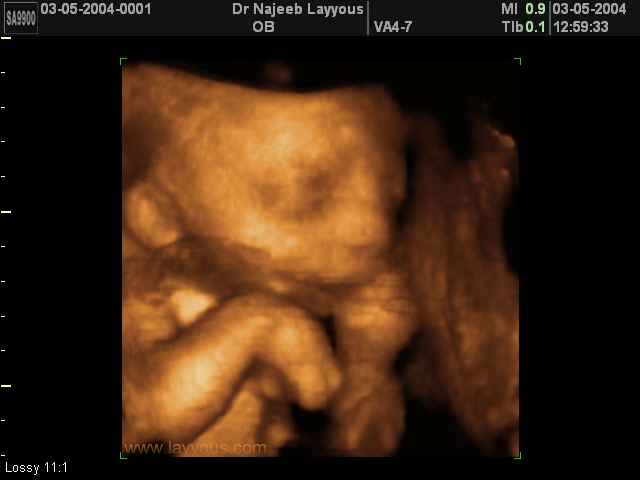

- لقطات فيديو للجنين بجهاز الموجات فوق صوتية رباعي الأبعاد

- صور لأطراف الجنين